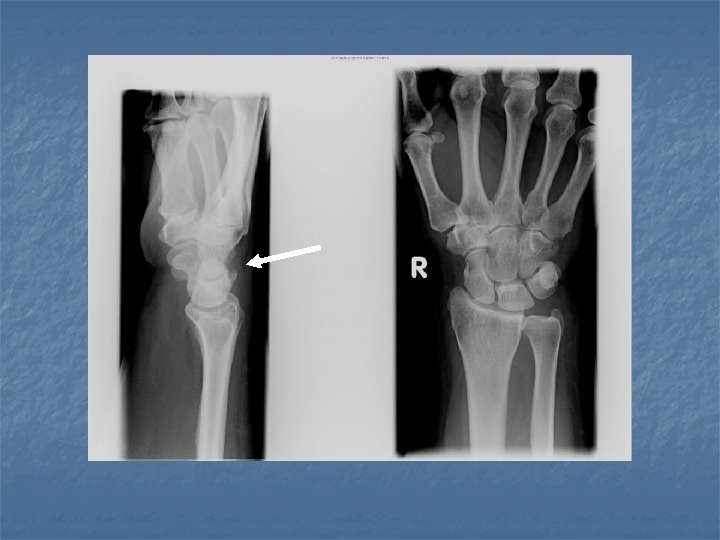

Perilunate dislocation n On lateral view: Dorsal or volar dislocation of the capitate. n Lunate remains in articulation with the radius although there may be some degree of tilt n n On dorsovolar view Crowdening of the proximal and distal carpal rows n Break in arcs II and III at the site of the capitate n

Lunate dislocation n On lateral view Axis of lunate is titled away from the articular surface of radius (spilled tea cup sign) n Capitate remains in normal alignment with radius and 3 rd metacarpal n n On dorsovolar view n Disruption of arc II while arc III remains intact